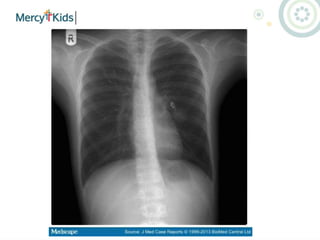

Bronchiolitis